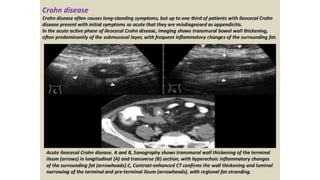

This document discusses the evaluation of right lower abdominal pain and lists appendicitis as a key cause. It notes that other potential causes include hemorrhagic cysts, heterotrophic pregnancy, salpingitis with pyosalpinx, funiculitis, and torsion of an undescended testis. The document was presented by Dr. A.S.M. Sufian of Cumilla Medical College Hospital and thanks the audience for their patience and listening.